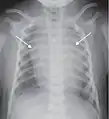

![]() A normal posteroanterior (PA) chest radiograph of someone without any signs of injury. Dx and Sin stand for "right" and "left" respectively. | |

A chest radiograph, chest X-ray (CXR), or chest film is a projection radiograph of the chest used to diagnose conditions affecting the chest, its contents, and nearby structures. Chest radiographs are the most common film taken in medicine.